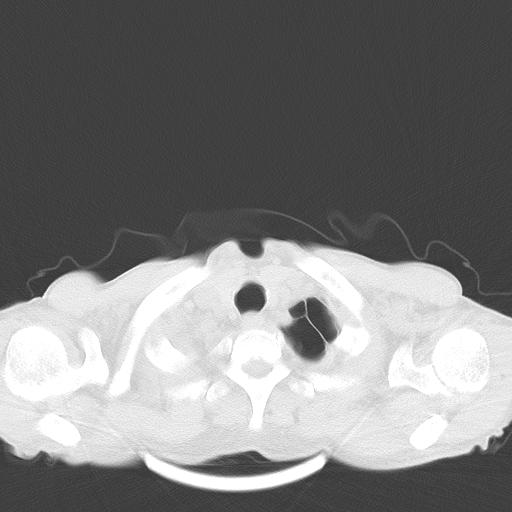

男性 75  咳嗽 一周前发热最高达39

右肺继发型tb并右侧tb性胸腔炎,右侧胸腔大量积液并右下肺膨胀不全,慢支肺气肿、多发肺大泡。建议抽胸水实验室检查并复查排除恶性在占位。

右上肺继发型肺结核,右胸腔中等量积液。

左上肺大泡。

结核的基础上有纵隔淋巴结肿大,右侧有胸水,但右侧纵隔反而窄,说明有肺有不张。

再就是右下肺有块影,和不张混合,还是不能除外肺癌。

补充材料,患者2月份ct片大致正常,双侧胸腔积液,2月份抽胸水未发现ca细胞,现患者发热,痰多,各气管通畅,